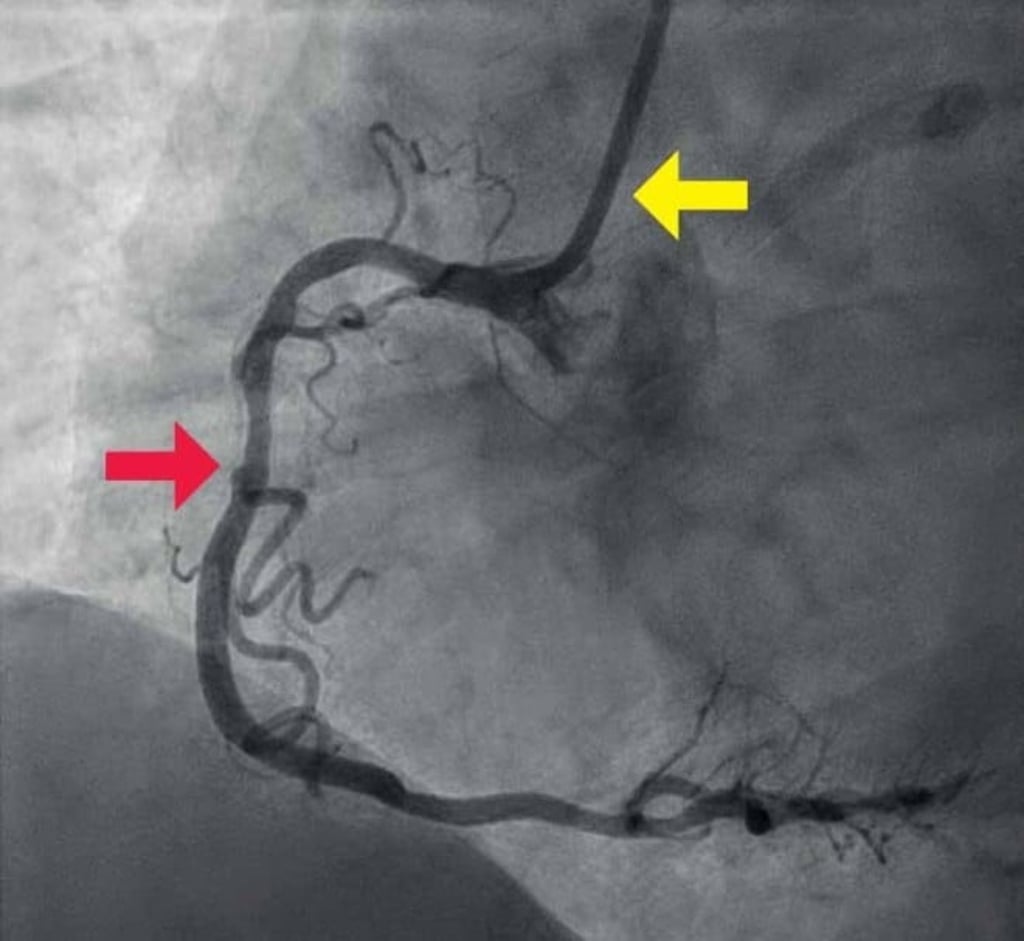

“We can now look at an artery from the inside with HD imagery that shows great details of the plaques. We can see whether they’re old or new, have calcium or are easy to rupture, which greatly improves our diagnostics,” said Dr. Cheong. This advanced imaging technique, called Optical Coherence Tomography (OCT), involves inserting a tiny and flexible catheter into the artery. Using lightwaves near infrared range, OCT allows the doctor to analyse the histology of the plaques(5).

“I have a patient who had a major heart attack in his 30s in London in the 2000s. He came to Hong Kong to work and I had to touch up on his stent procedure. Part of his vessels had plaque buildup so I prescribed both a statin and a PCSK9 inhibitor. Three years later, I looked at his artery again and the improvement was remarkable. There was less deposit on the artery wall and his cholesterol was reduced to a very low level,” said Dr. Cheong.